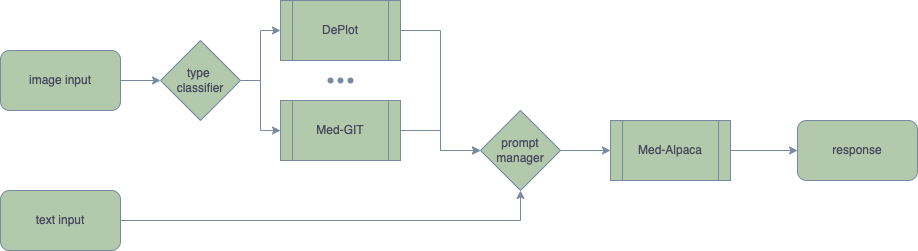

Domain-specific foundation models are crucial in the biomedical field as the language used in biomedical text is highly specialized and contains numerous domain-specific terms and concepts not found in general domain text corpora like Wikipedia and Books. Pre-training on significant amounts of biomedical text has been shown to enhance the performance of language models on various biomedical text mining tasks when compared to existing publicly available biomedical PLMs. However, with the large number of parameters in modern language models, the cost of fine-tuning even a 7B model solely on PubMed is too expensive for most academic institutions that lack sufficient computing resources. Pre-training models on extensive medical image datasets to acquire multi-modal abilities is even more costly. Therefore, more cost-effective techniques such as Adapter, Instruct-Tuning and Prompt Augmentation are being explored to develop a model that can be trained and deployed on gaming-level graphics cards while still possessing sufficient capabilities. Furthermore, there is no public multimodal foundation model designed for biomedical usage to the best of our knowledge. As a result, we are pleased to release the Visual Med-Alpaca, an open-source, multi-modal, biomedical foundation model. Visual Med-Alpaca uses a prompt manager to merge the textual and visual information into the prompt for generating responses with biomedical expertise. The model is fine-tuned using two distinct datasets to incorporate biomedical knowledge and visual modality. The process involves collecting inquiries from various medical datasets and synthesizing answers with a gpt-3.5-turbo model. The study involves the integration of visual foundation models, namely the DEPLOT and Med-GIT models, to accommodate medical images as inputs. The Med-GIT model is a GIT fine-tuned specifically on the ROCO dataset to facilitate specialized radiology image captioning. The training procedure for the model is available in the Github repository. Visual input is a critical element of the medical domain, and the system architecture is designed to facilitate the seamless integration of alternate medical visual foundation models. The model's architecture is developed to translate image to text, followed by a cognitive engagement in reasoning over the text thereby derived. The most important task in the future is to systematically evaluate the medical proficiency and potential defects of Visual Med-Alpaca, including but not limited to misleading medical advice, incorrect medical information, etc. In addition to the conventional use of benchmarking and manual evaluation, we hope to target different model users (doctors and patients) and evaluate all aspects of the model in a user-centred manner. It is also important to note that Visual Med-Alpaca is strictly intended for academic research purposes and not legally approved for medical use in any country. Resources: Please submit a request to access the checkpoints, tokenizer as well as a huggingface served demo. We apologize for the inconvenience, but this process may take extra time to go through ethical screening at Cambridge University. We will notify you as soon as we get necessary clearance.

Model Architecture and Training Pipeline

Domain Adaptation: Self-Instruct in Biomedical Domain

Visual Adaptation: Medical Image Captioning and Deplot

Visual input is a critical element of the medical domain, contributing essential information in healthcare settings. Healthcare practitioners heavily rely on visual cues to diagnose, monitor and treat patients. Medical imaging technologies, such as X-ray, CT and MRI, provide an unparalleled means of examining internal organs, identifying diseases and abnormalities that may not be visible to the naked eye.

Our study involves a further development of our previous work on visual language reasoning concerning charts and plots, as showcased in DEPLOT: One-shot visual language reasoning by plot-to-table translation. In this study, we enhance our approach by incorporating a visual foundation model that is capable of accommodating radiology images as inputs.

Within this particular framework, the task of visual language reasoning can be delineated into a bifurcation consisiting of two key phases: (1) the process of translating image to text, followed by (2) a cognitive engagement in reasoning over the text thereby derived.

The process involves the utilization of visual foundation models to convert medical images into an intermediate text state. The converted data is subsequently employed to prompt a pre-trained large language model (LLM), relying on the few-shot reasoning abilities inherent in LLMs.

At present, our platform is capable of supporting two distinct visual foundation models, namely the DEPLOT and Med-GIT models, considering the prevalence of plot and radiology imagery within the medical field. This system's architecture is also designed to facilitate the seamless integration of alternate medical visual foundation models.

The Med-GIT model represents a GIT: Generative Image-to-text Transformer for Vision and Language, fine-tuned specifically on the ROCO dataset to facilitate specialized radiology image captioning. The training procedure for the model is outlined in comprehensive detail in our publicly accessible Github repository.